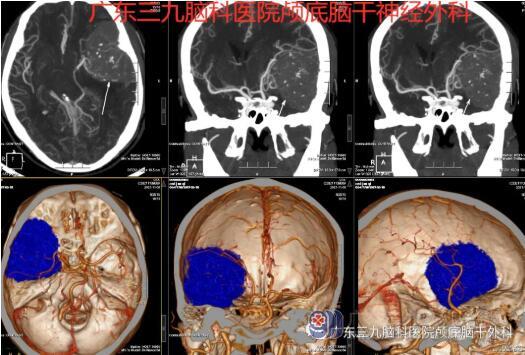

术前CTA

蔡先生住院后,主管医生与患者及家属充分沟通,其同意进行手术治疗。随后,由张良主任主刀,进行了左侧蝶骨嵴脑膜瘤切除术,术程顺利。病理报告示:脑膜皮细胞型脑膜瘤,CNSWHO 1级。

术前术后MR示左侧额颞顶部呈术后改变。